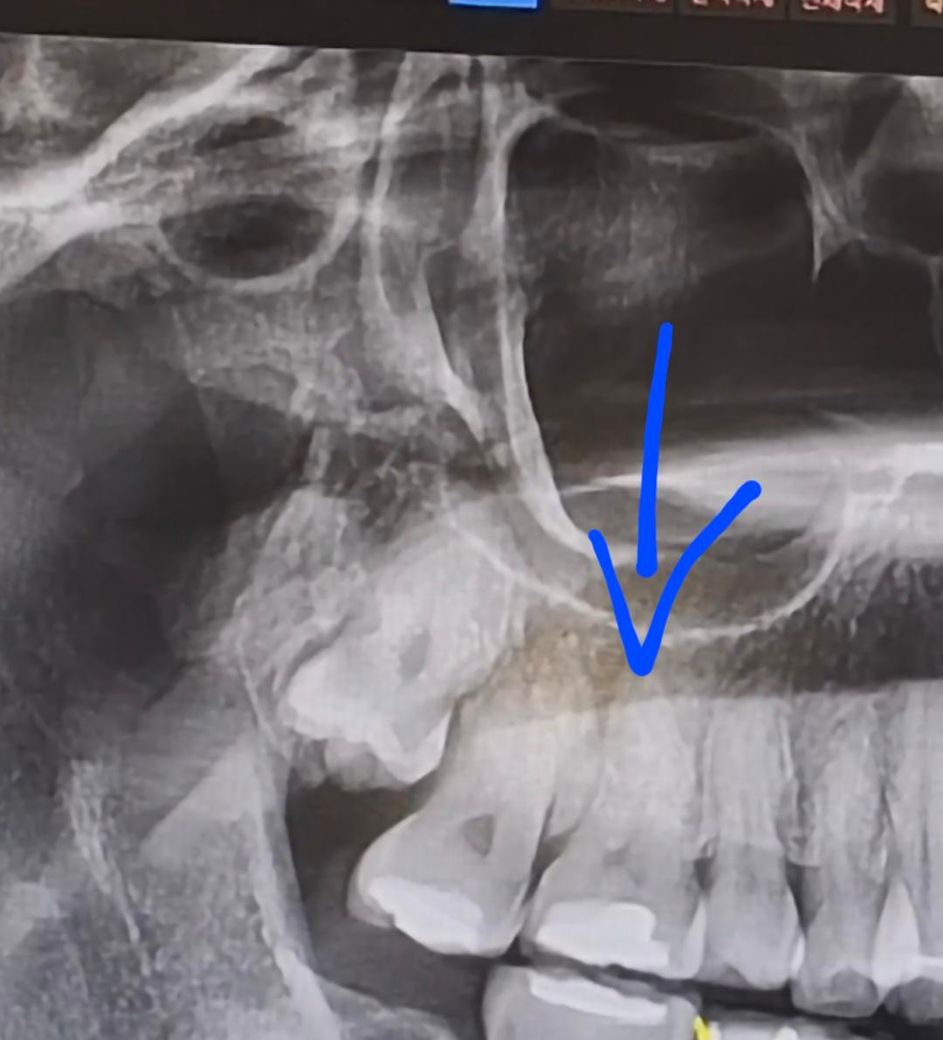

파란부분 치아빼고 그뒤에 치아가 파란색오고 매복 사랑니가 그 앞 어금니로 끌어쓸수 있나요?

아직 파란색 화살표의 치아는 빼야 할 상태는 전혀 아닙니다. 향후 문제가 생길 걸 가정해서 질문 주신 것 같은데요. 현실적으로 그렇게 정교하게 치아를 옮기기도 쉽지않고, 시간도 오래 걸리고 더군다나 안쪽 사랑니는 교정장치 붙이기도 아주 어렵고 유지도 잘 안될겁니다.